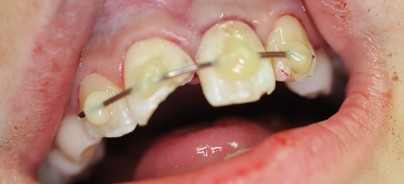

Am Tag des Unfalls wurde die Wurzeloberfläche des avulsierten Zahnes zunächst mit NaCl abgespült (Abb. 2). Die knöchern völlig intakte Alveole wurde ebenfalls mit NaCl gespült. Dabei ist darauf zu achten, dass das in der Alveole entstandene Koagulum vorsichtig und vollständig ausgespült wird, ohne dass die parodontalen ­Fasern und Zementoblasten verletzt werden (Abb. 3). Anschließend wurde der avulsierte Zahn 21 mittels einer Frontzahnzange in seine Alveole replantiert und mit ­einer Draht-Kunststoff-Schiene geschient (Abb. 4). Am vitalen frakturierten Zahn 11 wurden die pulpanahen Bereiche mit einem Kalziumhydroxidpräparat abgedeckt und dieses provisorisch mit einem Flow fixiert. Anschließend wurde eine Röntgenaufnahme zur Kontrolle der Replantation angefertigt (Abb. 5). Es wurde ein Rezept über ein Analgetikum sowie ein Antibiotikum ausgestellt. Für den folgenden Tag wurde ein Kontrolltermin in der Oralchirurgie sowie der erste Termin in der Zahnarztpraxis für Kinder bei Dr. Christina Masuck vereinbart.

Nach der Replantation wird der Zahn mittels einer Schiene stabilisiert. Hierfür eignet sich zum Beispiel die Draht-Kunststoff-Schiene. Die Okklusion wird vor der Befestigung der Schiene kontrolliert. Es reicht aus, jeweils einen unverletzten Nachbarzahn in die Schiene mit einzubeziehen (Ebeleseder K. A. et al. 1995). Die Schiene wird immer zuerst an den unverletzten Nachbarzähnen fixiert und zuletzt am replantierten Zahn. Bei entsprechender Schienung der Zähne heilt verletzter Knochen in der ­Regel innerhalb von vier bis sechs Wochen aus. Verletztes Weichgewebe heilt gewöhnlich innerhalb der ersten fünf bis zehn Tage aus. Die Schiene kann bereits nach ca. zwei Wochen wieder entfernt werden. Zu lange Schienungszeiten begünstigen eine Ankylose des replantierten Zahnes und damit auch das Risiko einer anschließenden Wurzelresorption. Die Trepanation sollte innerhalb der ersten sieben bis vierzehn Tage erfolgen. Da der Zahn in dieser Zeit noch geschient ist, wird die parodontale Einheilung durch die Trepanation nicht gestört. Kalziumhydroxid ist in der Endodontie als medikamentöse Einlage für die Behandlung infizierter Kanäle sowie für die Behandlung infektionsbedingter externer Resorptionen das Mittel der Wahl. Kalziumhydroxid hat allerdings keine Wirkung in Hinblick auf die initiale entzündliche Reaktion, die im Parodont eines replantierten Zahnes abläuft. Es kann sogar die parodontale Einheilung stören, woraus sich eine erhöhte Ankylosegefahr mit späterer externer Resorption ergibt. Somit sollte bei frühzeitiger Trepanation (während der parodontalen Regenerationsphase, innerhalb der ersten ein bis zwei Tage) besser auf ein Tetrazyklin-Kortikosteroid-Präparat (z.B. Ledermix®) ausgewichen werden. Studien an Affenzähnen haben gezeigt, dass die Verwendung von Ledermix® die initiale entzündliche Reaktion im Parodont und die Entstehung von externen Resorptionen beseitigen kann. Ledermix® hat nämlich einen direkten Einfluss auf die Dentinoklasten, welche inhibiert werden. Es hat aber keinen schädigenden Effekt auf parodontale Zellen (Pierce A., Lindskog S., 1987; Pierce A. et al. 1988, Bryson E. C. et al. 2002).